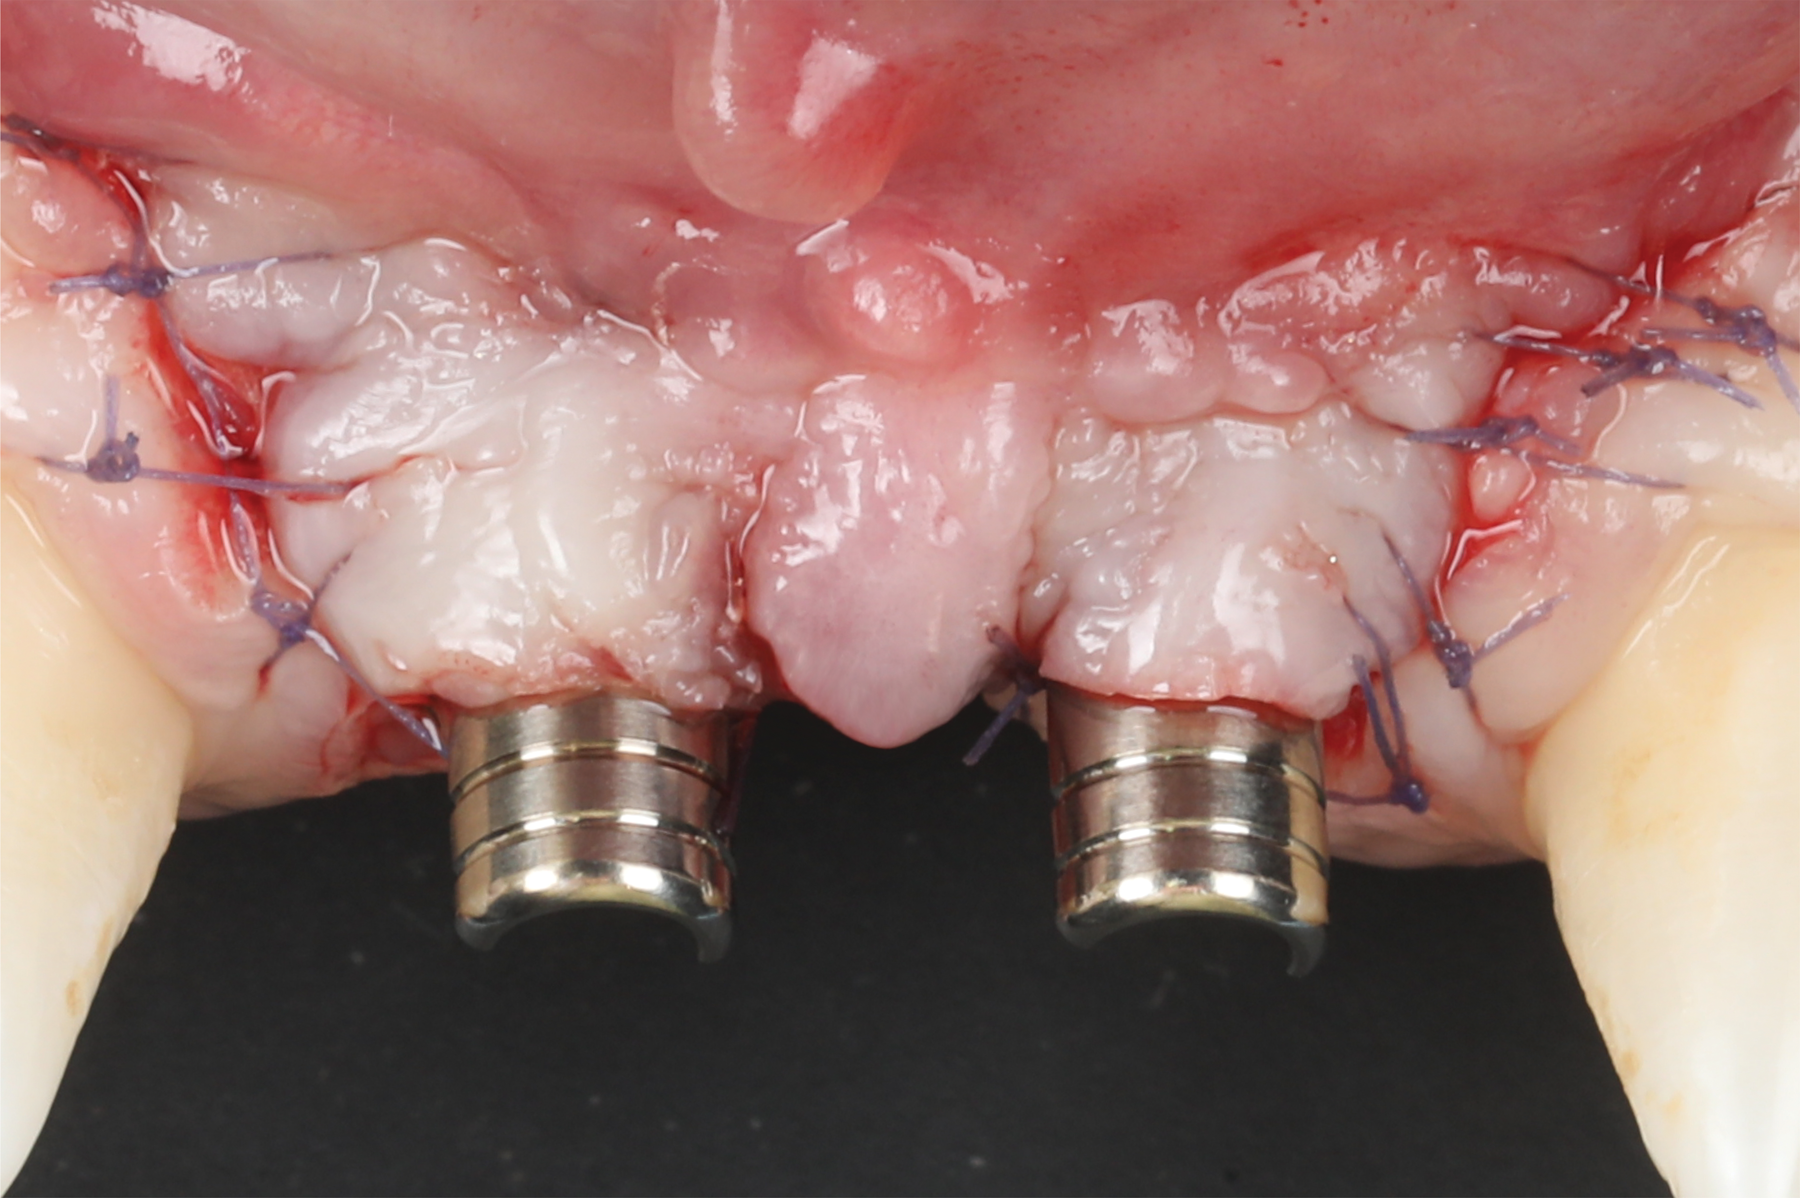

Oral hygiene instructions were reviewed with the patient and reinforced 6 weeks before the surgical visit. At the surgical appointment, the implant-supported crowns and abutments were removed, and two cover screws were inserted. A split-thickness trapezoidal-shape CAF was performed (Figure 3). The two slightly divergent beveled oblique incisions were placed between the implants and lateral incisors. A split-thickness flap was elevated, with meticulous care taken to maintain a layer of connective tissue adherent to the implant surface. Maintaining this layer of connective tissue on the implant body lacking buccal bone is an important step that differentiates flap elevation on healthy implants with PSTDs from implants with peri-implantitis (Figure 4).

After this elevation, the flap was released with a deep incision parallel to the bone and then with a superficial incision with the blade parallel to the external mucosal surface, until it was able to passively reach a position approximately 2 mm coronal to the ideal final level of the soft-tissue margin. The anatomical papillae between the implants and lateral incisors and the inter-incisive papilla were de-epithelialized with a microblade, not only on the buccal aspect but also in the occlusal region to enhance the vascular bed for the flap.

A free gingival graft was harvested from the palate and then extraorally de-epithelialized to obtain a dense and fibrous CTG (Figure 5). A collagen sponge was applied on the palatal donor site and stabilized with 5-0 polytetrafluoroethylene (PTFE) suture. A thin layer of cyanoacrylate tissue glue was applied on top of the collagen sponge, as described by Tavelli et al in 2019.14 No chemical or mechanical root conditioning agents were applied on the implant surface. The CTG was stabilized with simple interrupted sutures (7-0 polyglycolic acid [PGA], butterfly) to the de-epithelialized anatomical papillae on the coronal aspect and the periosteum on its apical portion (Figure 6). The flap was then coronally advanced and sutured by performing simple interrupted sutures (6-0 and 7-0 polypropylene) at the level of the vertical incisions and at the level of the palatal aspect, to completely cover the graft and cover screws (Figure 7).

Fig 3. Coronally advanced flap after removal of the crowns for soft-tissue augmentation.

Figure 3

Fig 4. Split-thickness flap elevation.

Figure 4

Fig 6. Stabilization of the connective tissue graft.

Figure 6

Fig 7. Submerged healing with flap closure.

Figure 7